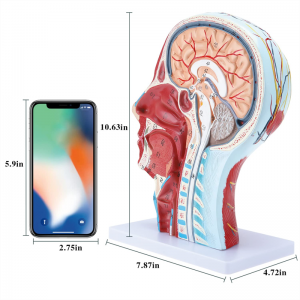

| ויסמעסטונג | 21 * 12 * 27 קם |

【1: 1 לייווז】 מידיאַן אָפּטיילונג פון 1: 1 נאַטירלעך גרויס קאָפּ & האַלדז אויבנאויפיקער נעוראַל וואַסקיאַלער מוסקל מאָדעל (רעכט זייַט). פייַן ווערקמאַנשיפּ. פאָרשלאָגן אַ פול קייט פון אַנאַטאַמיקאַל פֿעיִקייטן.

דער מאָדעל איז נאַטירלעך גרויס קאָפּ און האַלדז אויבנאויפיקער נעוראָוואַסקולאַר מוסקל מאָדעל, 1 קאָמפּאָנענט, ווייַזונג די דעטאַילס פון די מענטשלעך רעכט קאָפּ און מעדיאַן סאַגיטטאַלע אָפּטיילונג, אַרייַנגערעכנט די יקספּאָוזד בעשאָלעם און די מעדיאַל סטרוקטור פון די פּאַראָטיד דריז און אויבערשטער רעספּעראַטאָרי שעטעך, און די סאַגיטטאַל אָפּטיילונג סטרוקטור פון די סערוואַקאַל רוקנביין